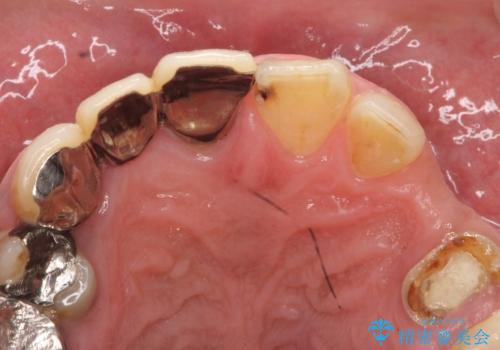

- 歯がない左側でものが咬めず、右側で咬むと歯が痛むので診て欲しいといらっしゃった方の症例です。

根尖病変が認められる歯は再根管治療を行い、歯根が破折していた左上4は抜歯しました。

インプラントは希望されなかったため、左側は1番から7番のロングスパンブリッジによる補綴を行いました。